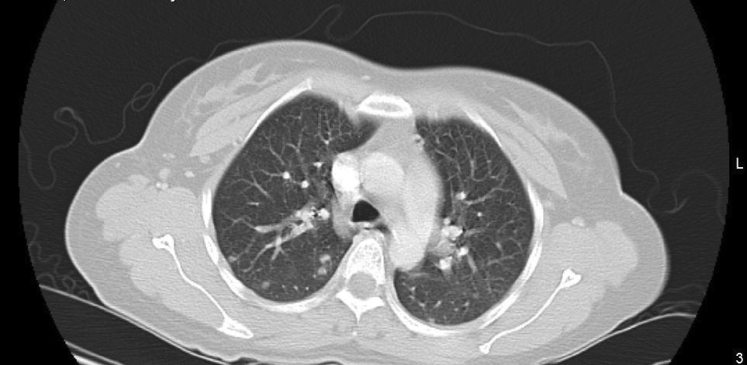

The patient continued to experience vaginal bleeding and her repeat hemoglobin level was 4.8 g/dL. She received 2 units of packed red blood cells. Because of her elevated beta-hCG without evidence of intrauterine pregnancy on ultrasound, additional testing was ordered for possible metastasis of GTN. CT imaging of her chest revealed small nodules, some with ground glass halos, scattered throughout both lungs (Figs. 1 and 2). These findings were interpreted by radiology as consistent with metastatic lung disease from choriocarcinoma.

Fig. 1.

Upper lung.